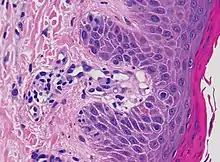

Interface dermatitis with lichenoid inflammation

| Main conditions[2] | Characteristics | Micrograph | Photograph |

|---|---|---|---|

| Generally/Not otherwise specified | Typical findings:[2]

|

||

| Lichen planus | Irregular epidermal hyperplasia with a jagged “sawtooth” appearance, compact hyperkeratosis or orthokeratosis, foci of wedge-shaped hypergranulosis, basilar vacuolar degeneration, slight spongiosis in the spinous layer, and squamatization. The dermal papillae between the elongated rete ridges are frequently dome shaped. Necrotic keratinocytes can be observed in the basal layer of the epidermis and at the dermal-epidermal junction. Eosinophilic remnants of anucleate apoptotic basal cells may also be found in the dermis and are referred to as “colloid or civatte bodies”. Whickham striae are usually seen in the areas of hypergranulosis. Vacuolar degeneration at the basal layer may be noted leading to focal subepidermal clefts (Max Joseph spaces). Squamatization occurs as a result of maturation and flattening of cells in the basal layer. It happens in areas of marked hypergranulosis with prominence of the sawtooth pattern of rete ridges. Wedge-shaped hypergranulosis can occur in the eccrine ducts (acrosyringia) or hair follicles (acrotrichia). In the hypertrophic subtype, the associated hyperkeratosis, parakeratosis, hypergranulosis, papillomatosis, acanthosis, and hyperplasia markedly increased with thicker collagen bundles forming in the dermis. Moreover, the rete ridges are more elongated and rounded as opposed to the typical sawtooth pattern. In atrophic LP, loss of the rete ridges and dermal fibrosis is prominent. In vesiculobullous LP, the disease progression is quicker. Hence, some of the distinctive features such as hyperkeratosis, hypergranulosis, or dense lymphocytic dermal-epidermal infiltrate may not be present. LP lesion may resolve with residual hyperpigmentation caused by a persistent increase in the number of melanophages in the papillary dermis.[9] | ![]() | ![]() |